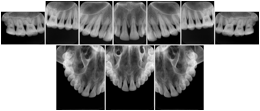

OO.1.4 Radiology

• A radiologist on his PACS assembles a screen layout of a stack of CT images of a current lung study, a secondary capture of a 3-D rendering of the CT, and a prior chest radiograph for the patient. He adjusts the window width / window level for the CT images, and zooms and annotates the radiograph to clearly indicate the tumor. He saves a Structured Display object representing that screen layout, including Grayscale Softcopy Presentation State objects for the CT WW/WL and the radiograph zoom and annotation. During the weekly radiology department conference, on an independent (non-PACS) workstation, he accesses the Structured Display object, and the display workstation automatically loads and places the images on the display, and presents them with the recorded WW/WL, zoom settings, and annotations.

• A mammographer reviews a screening exam on a mammo workstation. She wishes to discuss the exam with the patient's general practitioner, who does not have a mammo-specific workstation. She saves a structured display, with presentation states for each image that replicate the display rendered by the mammo workstation (scaling, horizontal and vertical alignment, view and laterality annotation, etc.).

Mammography Structured Display

Figure OO-7. Mammography Structured Display